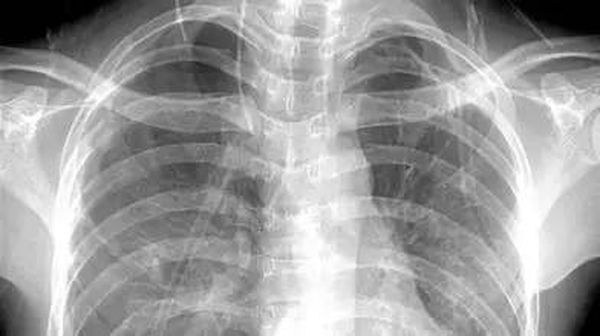

X线

像把面包压扁了看

X线会穿过人体,遇到被遮挡的部位,底片上不会曝光,洗片后这个部位就是白色的。

就像一片面包或一块棉花,看不到里面的纤维纹理,但用手压瘪了会清晰一些。X线最大缺点是受制于深浅组织的影像相互重叠和隐藏,有时需要多次多角度拍摄X线片。

胸部——粗看X线片,细看CT,看肺不要选核磁

X线胸片可粗略检查心脏、主动脉、肺、胸膜、肋骨等,可以检查有无肺纹理增多、肺部钙化点、主动脉结钙化等。

胸部CT检查显示出的结构更清晰,对胸部病变检出敏感性和显示病变的准确性均优于常规X线胸片,特别是对于早期肺癌确诊有决定性意义。但是CT检查的辐射剂量高于X线。核磁对于肺部疾病的诊断,应用非常有限。